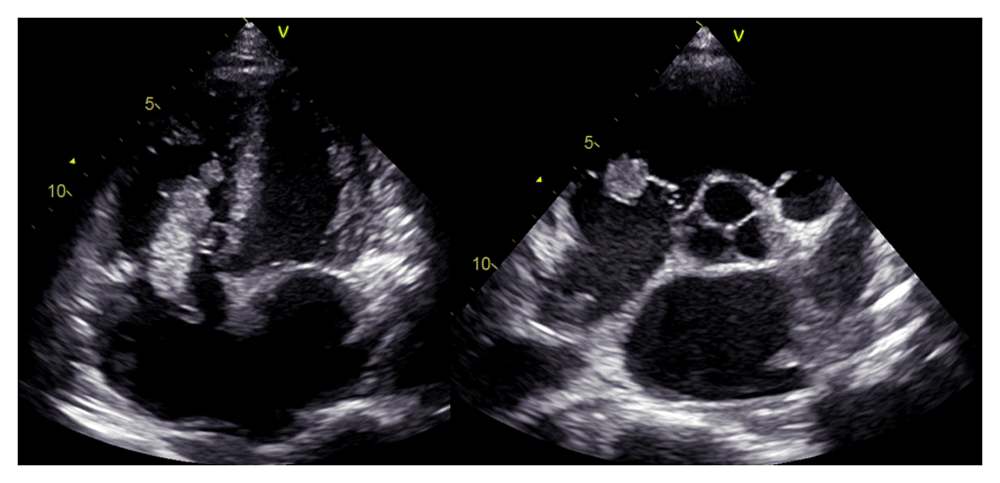

In laboratory findings, serum electrolytes revealed hypokalemia (K: 3.3 mmol/L; normal range 3.5–5.1 mmol/L), serum protein showed hypoalbuminemia (albumin: 3.1g/dL; normal range 3.4–5.0 g/dL), while other parameters were between normal limits. An electrocardiogram (ECG) showed sinus tachycardia rhythm 125 bpm, right-sided frontal axis, horizontal axis clockwise rotation, and slow progression of R waves at V1–V4 (Figure 1). A chest X-ray showed cardiomegaly, pulmonary congestion, and minimal bilateral pleural effusion (Figure 2). Echocardiographic examination revealed moderate mitral regurgitation (dilated mitral annulus), dilatation of all cardiac chambers (LVIDd 5.8 cm), visible thrombus in IVC to RA, decreased left and right ventricular systolic function (EF teich 35%, TAPSE 1.3 cm), and global hypokinetic of the left ventricle with eccentric LVH. The scans from a transthoracic echocardiogram (TTE) showing thrombus is shown in Figure 3 and Figure 4.

A chest CT scan (Figure 5) showed right pulmonary artery embolism at ± 5.9 cm from bifurcation on the anterior side of the intermediate right bronchus; emboli on the left pulmonary artery bifurcation and the left pulmonary artery basal part; multiple right intraatrial hypodense lesions not showing contrast enhancement leading to a visualization of the right intraatrial thrombus; pulmonary infarction in the lateral-posterior segment of the base of the inferior lobe of the right lung, the lateral-posterior segment of the base of the inferior lobe of the left lung, and the anterior segment of the superior lobe of the left lung; and superior vena cava thrombus at VTH level 1-5. Figure 6 shows the protruded thrombus in the right atrium passing through the tricuspid valve. TTE also showed the position of the thrombus moving from the inferior vena ca va towards the right atrium (Figure 7). The movement of the large protruding thrombus can be seen in supplementary video files 1–35–7.